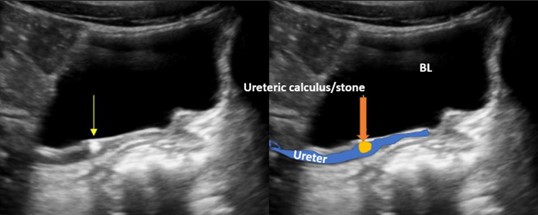

6. kép:

Húgyvezeték kő 1.

Ezen a képen egy követ láthatunk az ureter kezdeti szakaszán (fehér nyíl). Az előtte lévő szakasz valamint a vese medence tágabb.

7. kép:

Húgyvezeték kő 2.

Ezen a képen a húgyvezetékben látható szintén egy kő, közvetlenül a húgyhólyag előtt. A sötét struktúra ami a kép felső részén helyezkedik el maga a húgyhúlyag (BL). Alatta látható a tágult húgyvezeték és benne a tágulatot okozó kő, ami világos (echodús) megjelenésű (sárga nyíl).